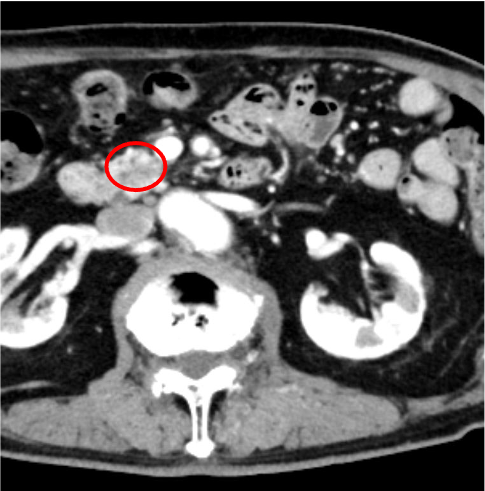

膵癌は、乏血性の境界不明瞭な腫瘤で、造影後期相で漸増性濃染を示すとともに、上流側主膵管の拡張を示すが、本症例はこの典型像に合致していた。主膵管拡張を来す乏血性の腫瘤の鑑別としては、groove pancreatitisなどの良性病変もあるが、膵頭部癌との鑑別は非常に困難とされており1)、疑わしい症例は早期に内視鏡下生検などの精査を依頼するのが望ましい。

本症例では造影CTにて膵頭部に乏血性病変を認めた。Vater乳頭部にも近接していたため、胆膵内視鏡(ERCP)にて検体採取が可能と判断し、病理学的精査を推奨した。消化器内科にて超音波内視鏡下生検(EUS-FNA)を施行、浸潤性膵管癌(invasive ductal adenocarcinoma)の診断が確定した。近傍のSMAへの浸潤はなく、遠隔転移もなかったことから切除可能であり、約7週間後に消化器外科にて膵頭十二指腸切除術を実施、その後順調な経過をたどっている。